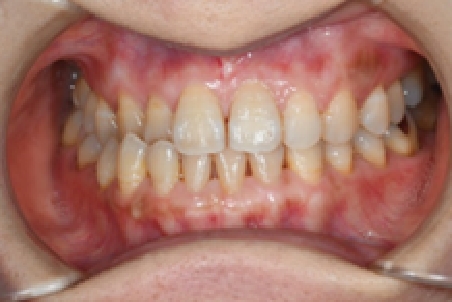

術前

術後

| 主訴 | 結婚式までに歯の色をきれいにしたい |

|---|---|

| 治療方法 | かぶせ物を外して、歯の土台の形を整えて、かぶせ物の型取りをします そして新しいかぶせ物を入れます |

| 使用素材 | セラミック |

| リスク副作用 | 硬いものを噛むとセラミックが割れる可能性がある |

| 金額(税込) | 1本 99,000円~165,000円 |

| 患者の年齢・性別 | 20代女性 |

| 治療期間 | 約1ヶ月 |